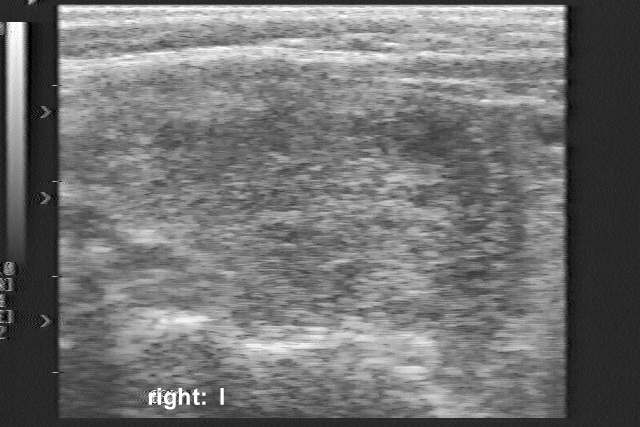

Ultrasonography: a moderately hypoechogenic nodule with lobulated margins occupied almost the entire right thyroid.

The sonographic images are naturally out of date. Nevertheless, the lobulated margins of the nodule are remarkable.